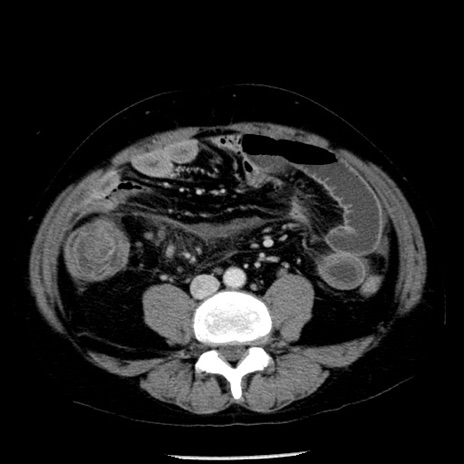

症例29(横断像)

【症例】40歳代男性

【現病歴】2日前から胃痛あり。徐々に周期的な激痛に変化した。本日になっても激痛があるため受診。

【身体所見】意識清明、BT 38-39℃台あり、腹部:膨満、やや硬、右下腹部に圧痛あり。

【データ】WBC 8500、CRP 23.26